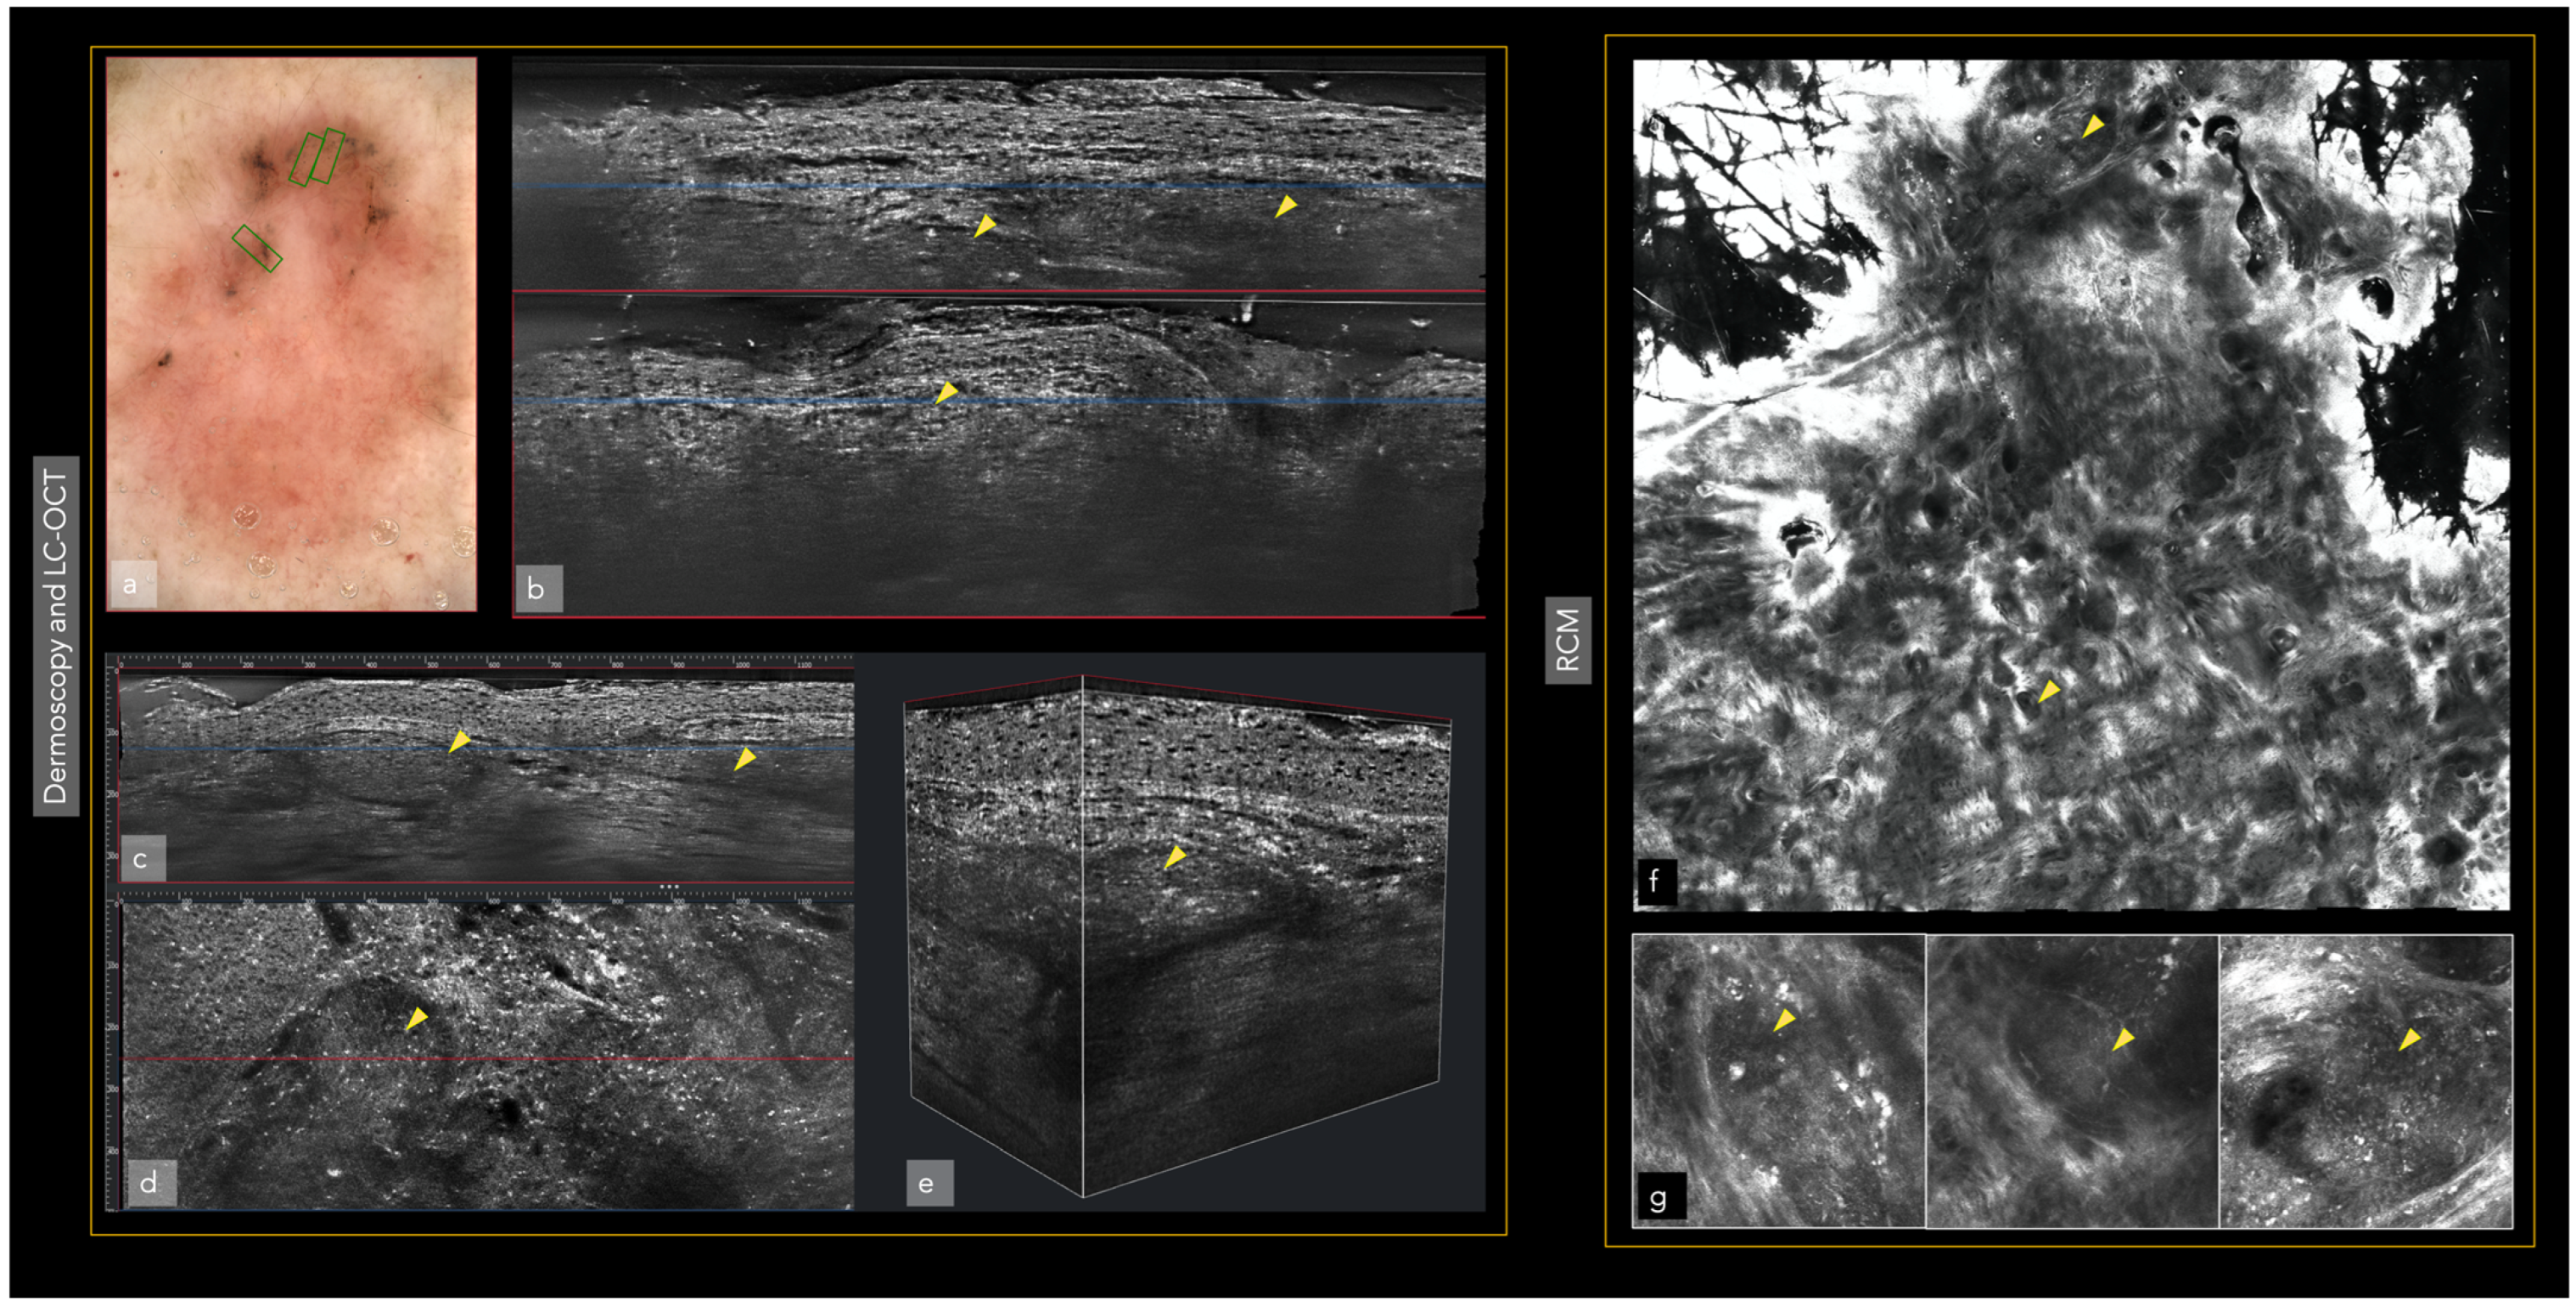

Different imaging techniques are represented in Figure 1 and Figure 2, in which the same superficial and infiltrating basal cell carcinoma has been studied with different in vivo techniques.

Figure 2.

The same superficial and infiltrating basal cell carcinoma in the left arm also studied with LC-OCT and RCM. Tumor presence (yellow triangles). Blue and red lines are the same area represented in the vertical (blue) and horizontal (red) view of LC-OCT: (a) Dermoscopy; (b) Vertical view of LC-OCT; (c) Vertical view of the tumor islands in LC-OCT; (d) The same area observed in the horizontal view of LC-OCT; (e) 3D view at the same level; (f) RCM revealing superficial and infiltrating basal cell carcinoma; (g) RCM tumoral details of the superficial component of the basal cell carcinoma.